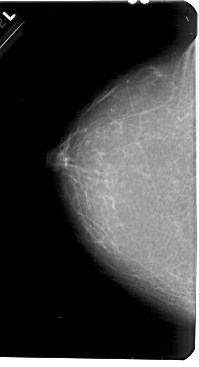

A_1680_1.LEFT_MLO

A_1680_1.LEFT_CC

LEFT_CC LINES 5491 PIXELS_PER_LINE 2971 BITS_PER_PIXEL 12 RESOLUTION 43.5 NON_OVERLAY

LEFT_MLO LINES 5491 PIXELS_PER_LINE 3241 BITS_PER_PIXEL 12 RESOLUTION 43.5 NON_OVERLAY